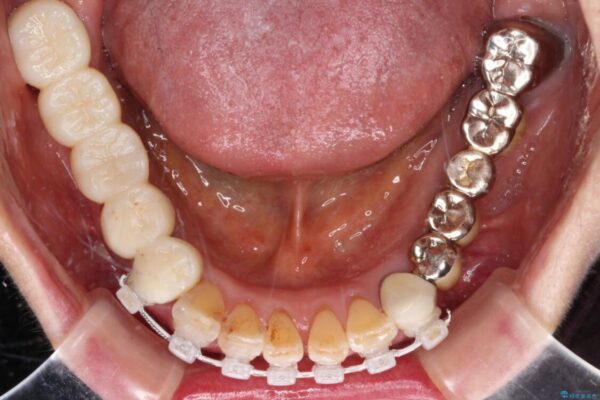

処置を予定していた歯を仮歯に変えた時点で、下顎前歯の部分矯正を行うかどうかを尋ねたところ、折角なので行いたいと言うことでしたので、矯正治療を行うこととしました。

インプラント埋入や根管治療治療など、治癒に一定の期間を要する処置の合間に矯正治療を行うことで、効率的に治療を進めて行くことができました。

治療途中

• 前歯をきれいにしたい インプラントや部分矯正を用いた総合歯科治療 治療途中画像